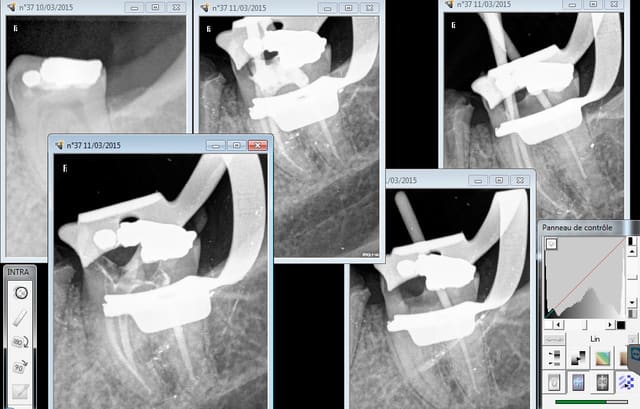

Les 2 endos molaire de la matinée. peut etre pas aussi bien faites qu'un endo exclusif, mais en 45 mn pour 81, 94 euros c'est pas mal. le patient va etre remboursé de l'intégralité.

Le rattrapage se fait sur les ic-coiffes actes également remboursés en intégralité. L'argent ne fait pas tout , hein ? -))))

Par contre si j'en foire une ( en général un r25 pété Sur 1-2 mm à l'apex) je veux bien te l'envoyer. C'est rare je te rassure. bon courage ! -)))))

Capture d e cran 2015 03 11 20.46 - Eugenol

Capture d e cran 2015 03 11 20.51 - Eugenol